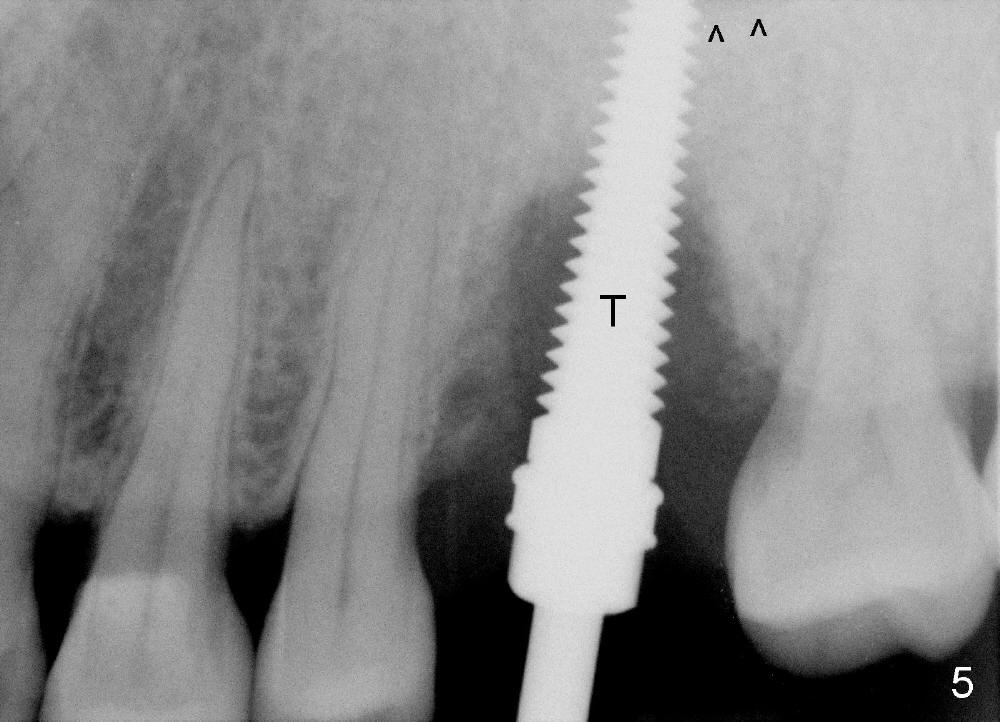

Fig.5: A 4.5x20 mm tap is inserted into the apical new dense bone (just past the sinus floor (^)).